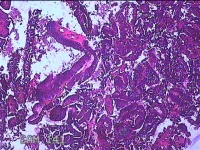

宫内物

性别

女

年龄

34岁

临床诊断

异常子宫出血

一般病史

阴道不规则流血1月余。

标本名称

大体所见

灰白暗红色不规则碎组织4.8x4.3x1.3cm一堆。